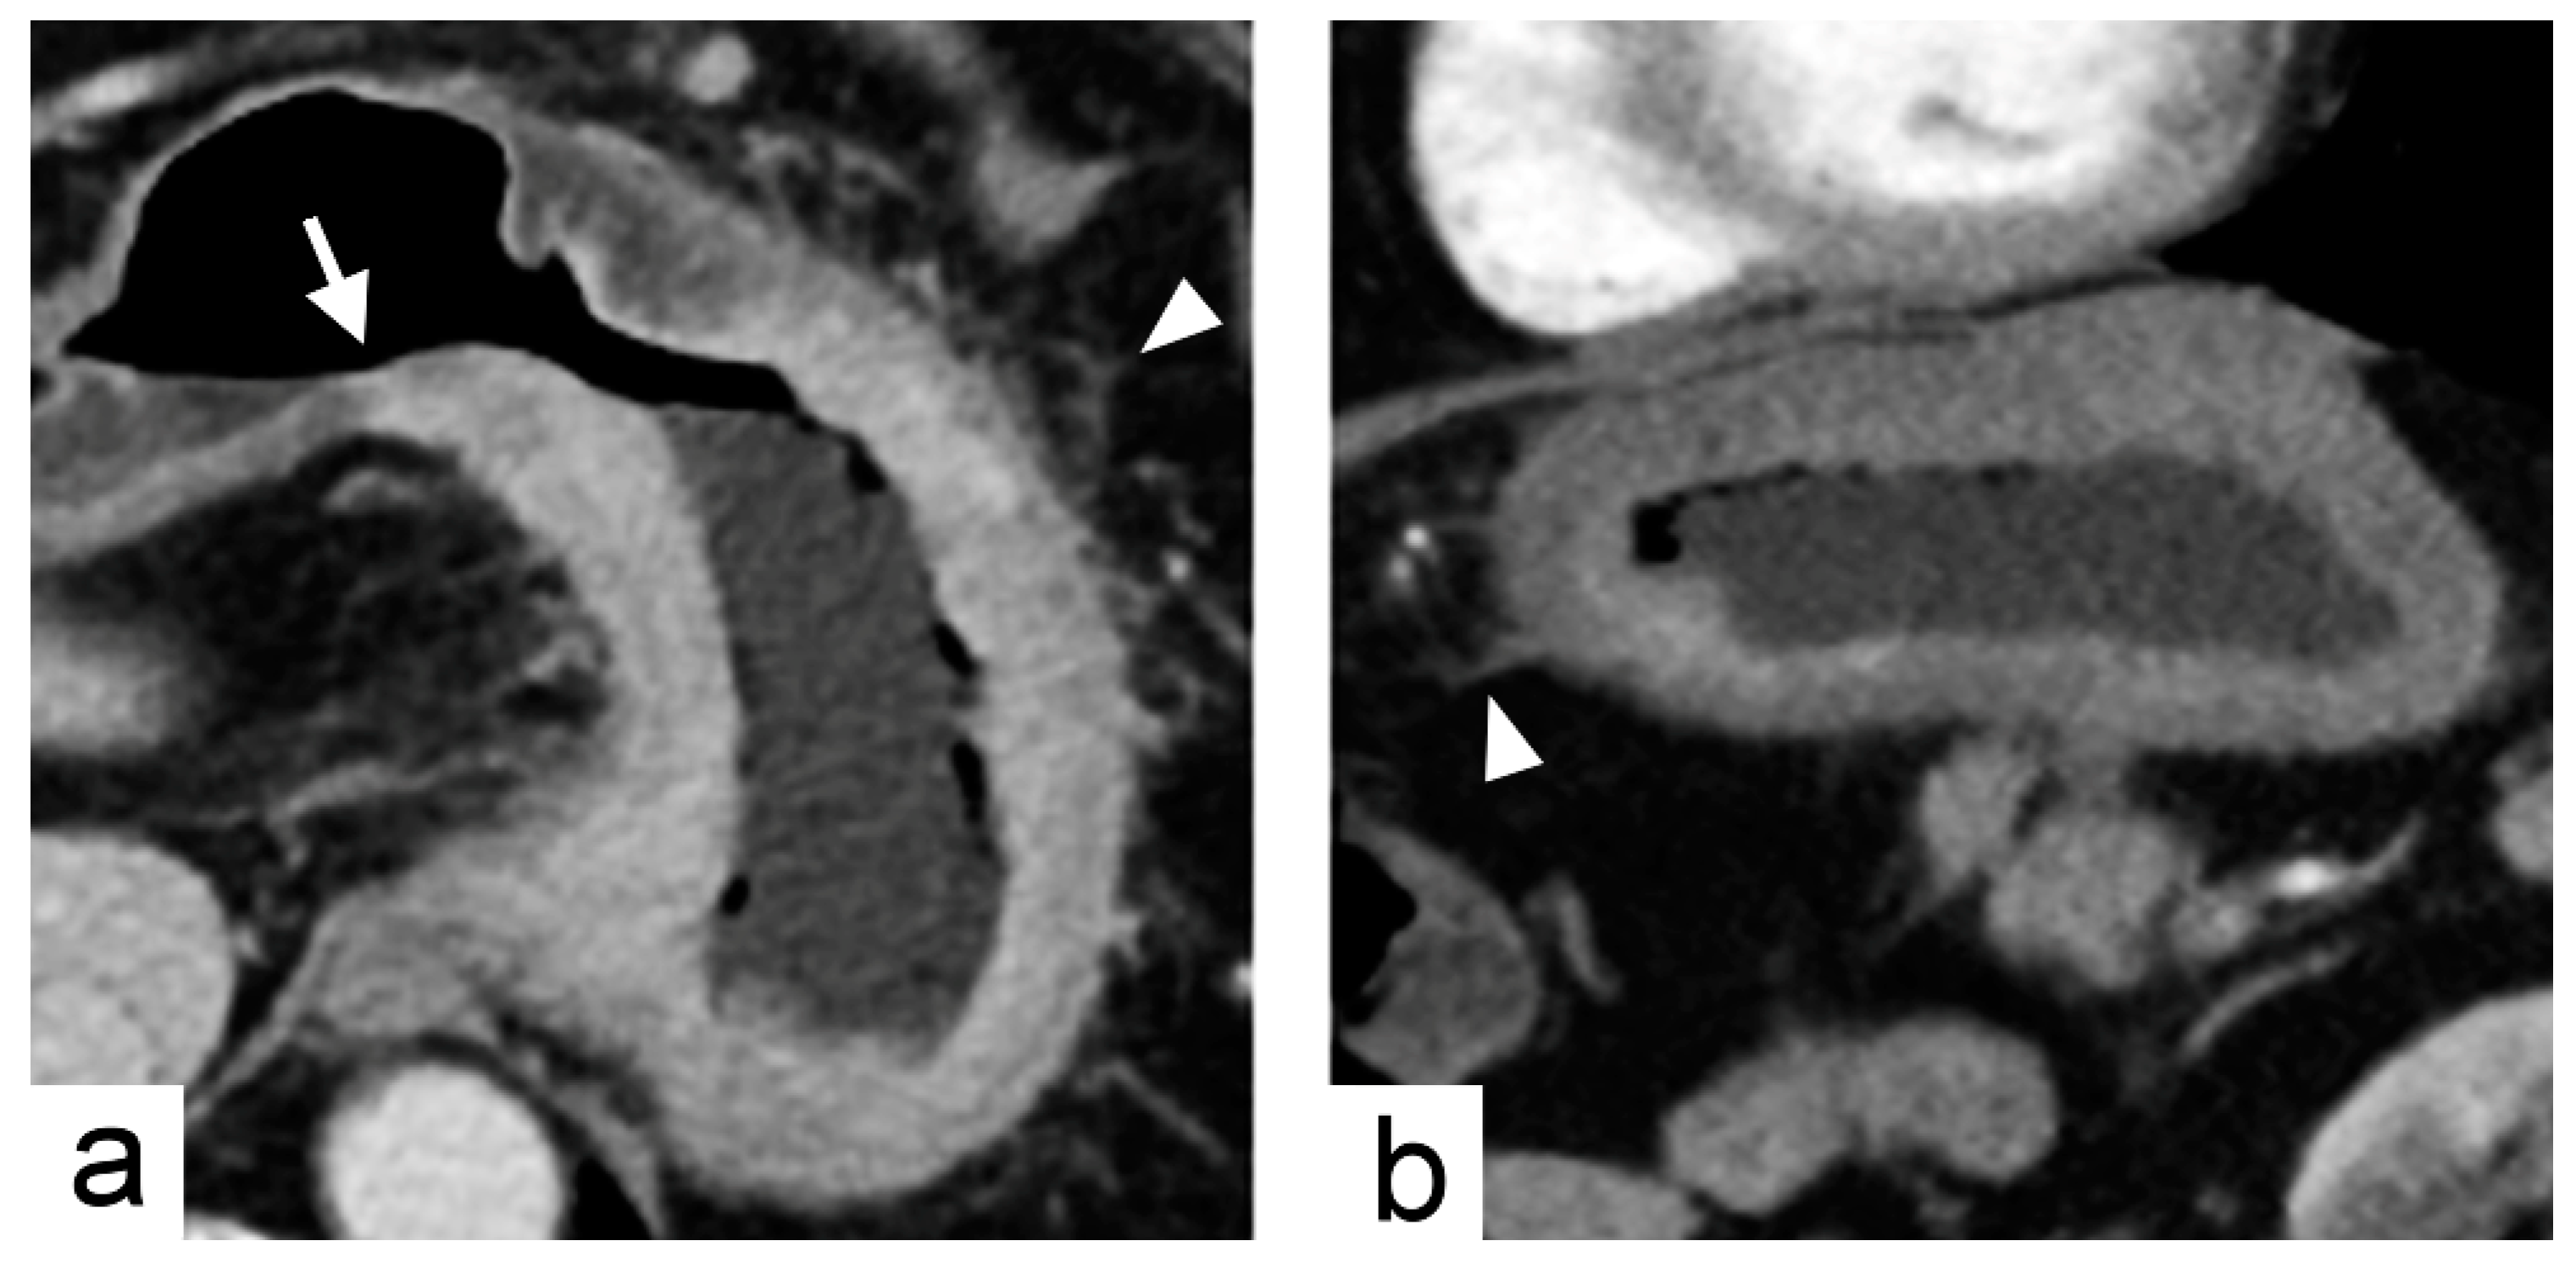

| Tumor transition angle | Transition angle between the tumor and the adjacent normal gastric wall defined as acute or obtuse angle | Binary | |